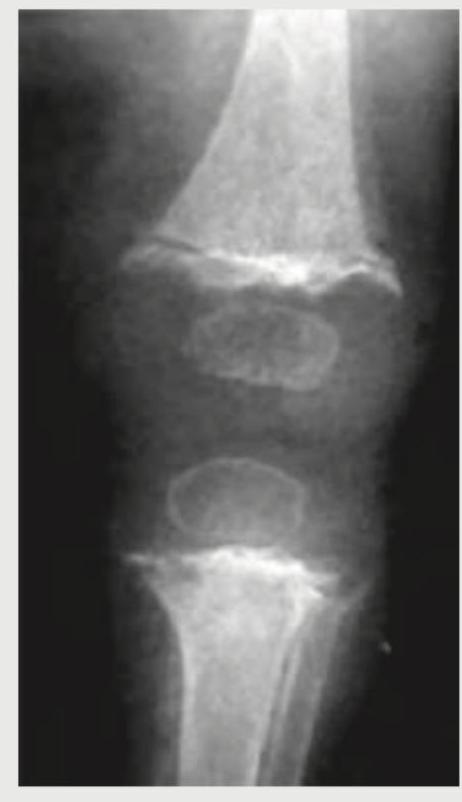

A 12-year-old boy presents with chronic knee pain for 2 years. A knee X-ray is shown. What is the probable diagnosis?

Explanation: ***Rickets*** - Classic X-ray findings include **metaphyseal cupping and fraying** at the growth plates, **widening of growth plates**, and **osteopenia**, which are characteristic of vitamin D deficiency in children. - Chronic knee pain in a **12-year-old** with these imaging changes strongly suggests rickets, as growth plates are still active at this age. *Chronic osteomyelitis* - Would show **bone destruction**, **sequestrum formation**, and **sclerotic changes** on X-ray, not the metaphyseal changes seen in rickets. - Typically presents with **fever**, **localized warmth**, and **acute onset** rather than chronic pain alone. *Osteosarcoma* - X-ray would demonstrate a **destructive bone lesion** with **sunburst pattern** or **Codman's triangle**, not metaphyseal cupping. - Usually presents as a **rapidly growing mass** with severe pain that worsens at night, unlike the chronic presentation described. *Hyperparathyroidism* - Causes **subperiosteal bone resorption** and **brown tumors** on X-ray, not the metaphyseal changes characteristic of rickets. - More commonly affects **adults** and presents with **hypercalcemia symptoms** like kidney stones and psychiatric symptoms.